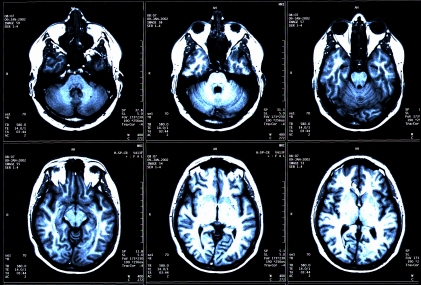

The VirtualScopics technology involves automated, quantitative analysis of images produced by CT and MRI scans – for example measuring objectively the size of tumors, and tracking how the size changes with time following treatment.

Currently, the approach is used in clinical studies, for example to monitor drug efficacy. But the company wants to extend that range of application. “Through this investment, the company intends to bring quantitative imaging to individual physicians and patients, and believes it will have a significant impact in the personalization of medicine, and in certain therapeutic areas that offer the potential for early diagnosis,” said VirtualScopics in a statement announcing the new funding.

The injection of cash will be used to validate the application of the approach for blood perfusion and oncology studies, and also to establish a new analysis platform aimed at diagnostics and personalized medicine.